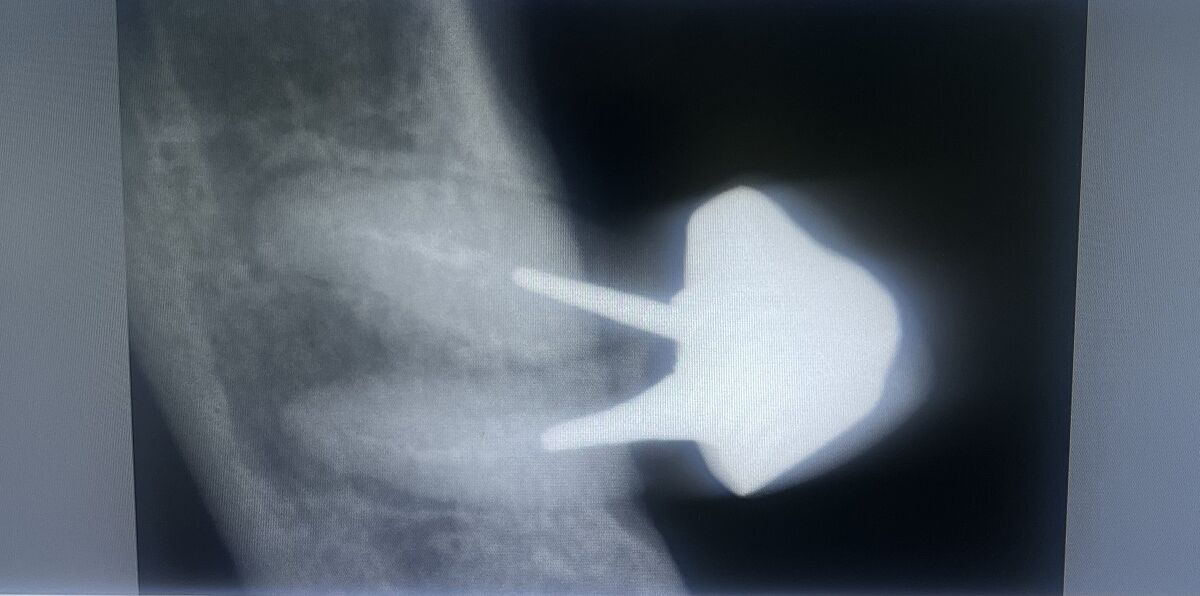

Есть стоматологи, гляньте снимок пожалуйста!!!

Зуб 7 под коронкой, болит, можно его спасти или нужно удалять

Я так поняла что каналы полупустые , но нет гнойных мешков

Предварительно, шанс есть. КТ точнее даст прогноз. Но никто гарантировать результат не сможет. Часто и удаляют, чтобы получить более предсказуемый результат в дальнейшем

Судя по снимку, там рядом тоже нет зуба. И в импланте ничего страшного нет

Именно в область этого зуба - нельзя. Там большая гранулема (разрушена кость), плюс к этому - стадия обострения

Всегда есть выбор. Обычно выбор делает хозяин зуба. А врач должен рассказать плюсы и минусы каждого варианта. Перспектива удаления у этого зуба велика. Например, в нашей клинике попытка лечения такого зуба стоила бы приблизительно, как и имплантация. Только на лечение гарантии нет, а на имплант 5 лет гарантии. Но если есть желание и деньги, то можно и рискнуть...